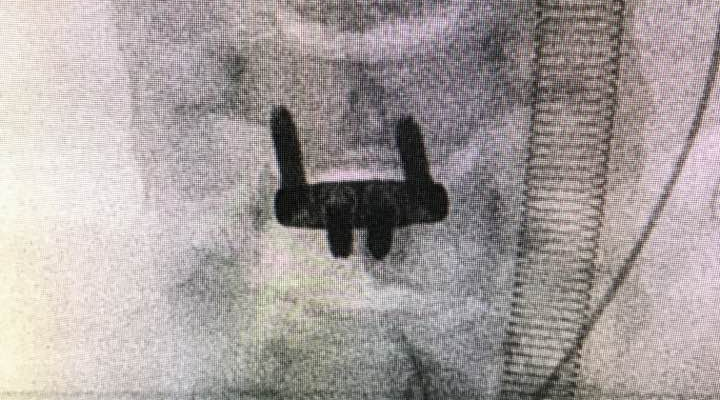

腰椎间孔椎间融合术(TLIF)